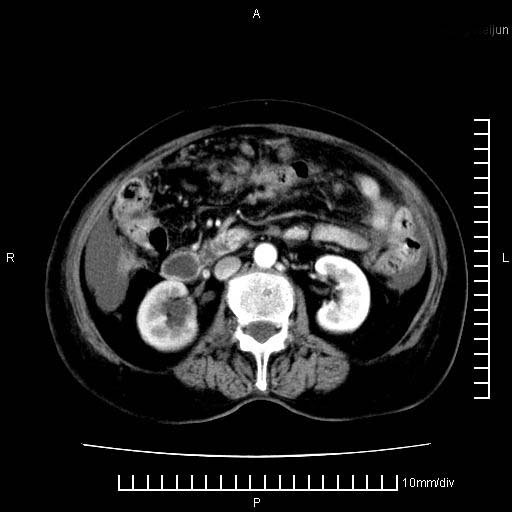

标题: CT28280:腹部增强:女性,80岁

上腹疼痛月余,外院核磁诊断胰腺癌。现临床示右下腹可明显触及包块,可片子上怎么没有看到?

1.胰腺颈体部癌。

2。腹腔积液。

4。右肾盂囊肿。

胰腺体部癌累及周围器官,腹膜、粘连

1。胰腺ca伴腹膜腔转移

2。肝左叶低密度灶,考虑转移可能

支持胰腺癌肝内转移,腹水改变。

胰腺结构模糊,胰尾部见囊性包块,周围脂肪密度增高,左肾前筋膜增厚,胸水、腹水。不符合胰腺ca伴腹膜腔转移。考虑胰腺炎伴假性囊肿形成、胸腹腔积液。

右肾盂囊肿。

1、考虑胰腺癌伴腹膜腔转移,胸腹水。

2、肝脏转移可能。

3、右肾盂囊肿。

1)考虑胰腺癌并胰腺假性囊肿形成。2)肝内低密度灶,不排除转移。3)右肾盂积水。4)腹水。5)右侧胸腔积液并右肺下叶部分膨胀不全。

考虑胰腺ca伴腹膜腔转移、肝左叶转移、右肾积水。右胸腔积液。